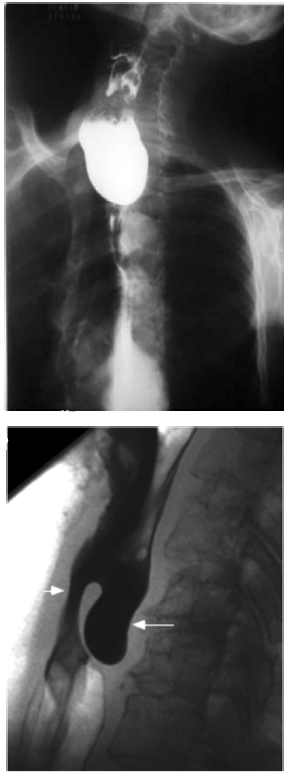

Disponível em: <www.scielo.br>. Acesso em: 16 fev. 2023.

Um paciente de 71 anos de idade apresentou queixa de disfagia cervical, associada a deglutição ruidosa, regurgitação, abaulamento cervical esquerdo, acessos de tosse, halitose e emagrecimento progressivo há três anos. Ele, então, procurou o cirurgião de cabeça e pescoço para investigar essa sintomatologia, o qual optou pela realização de exames de imagem, que evidenciaram as imagens apresentadas.

Qual é a hipótese diagnóstica mais plausível?

A aorta (ponta de seta aberta) e a artéria mesentérica superior (ponta de seta fechada)

Disponível em: <www.uptodate.com>. Acesso em: 16 fev. 2023.

Uma paciente de 21 anos de idade, caucasiana, com IMC atual = 16.1 Kg/m2, apresentava, há seis meses, intolerância alimentar acompanhada de náuseas e vômitos pós-prandiais. Essas queixas eram muitas vezes associadas a digestões prolongadas e dor epigástrica, que eram aliviadas com o vômito. O início do quadro clínico surgiu após episódio de gastroenterite aguda, ocorrendo uma perda ponderal de 16% em 120 dias. Com o decorrer dos meses, a situação clínica foi agravada com o aumento da intolerância alimentar e maior perda de peso, embora a paciente procurasse se alimentar. Optou-se, assim, pela realização de exames de imagem abdominal.

Associando-se a imagem apresentada ao quadro previamente descrito, qual é a principal hipótese diagnóstica?